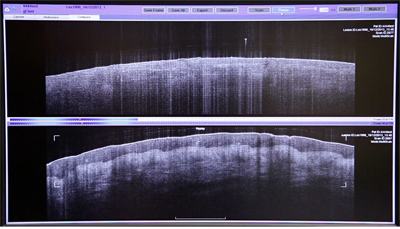

VivoSight is a point-of-care tissue-imaging system that for the first time allows users to see below surface of the skin; non-invasively and with continuous high definition images. Using VivoSight, medical professionals can non-invasively obtain images of the epidermis and superficial dermis of the skin and make an accurate, pain-free diagnosis in real-time.